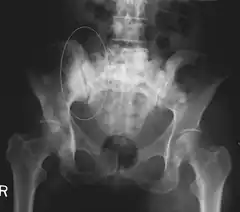

| 3D rendered CT scan of bone metastases of the hip bone, in a 60 year old woman with parotid gland cancer. Large lesions are seen on the ilium on the more distant side. Involvement of the vertebral column has caused a compression fracture. | |